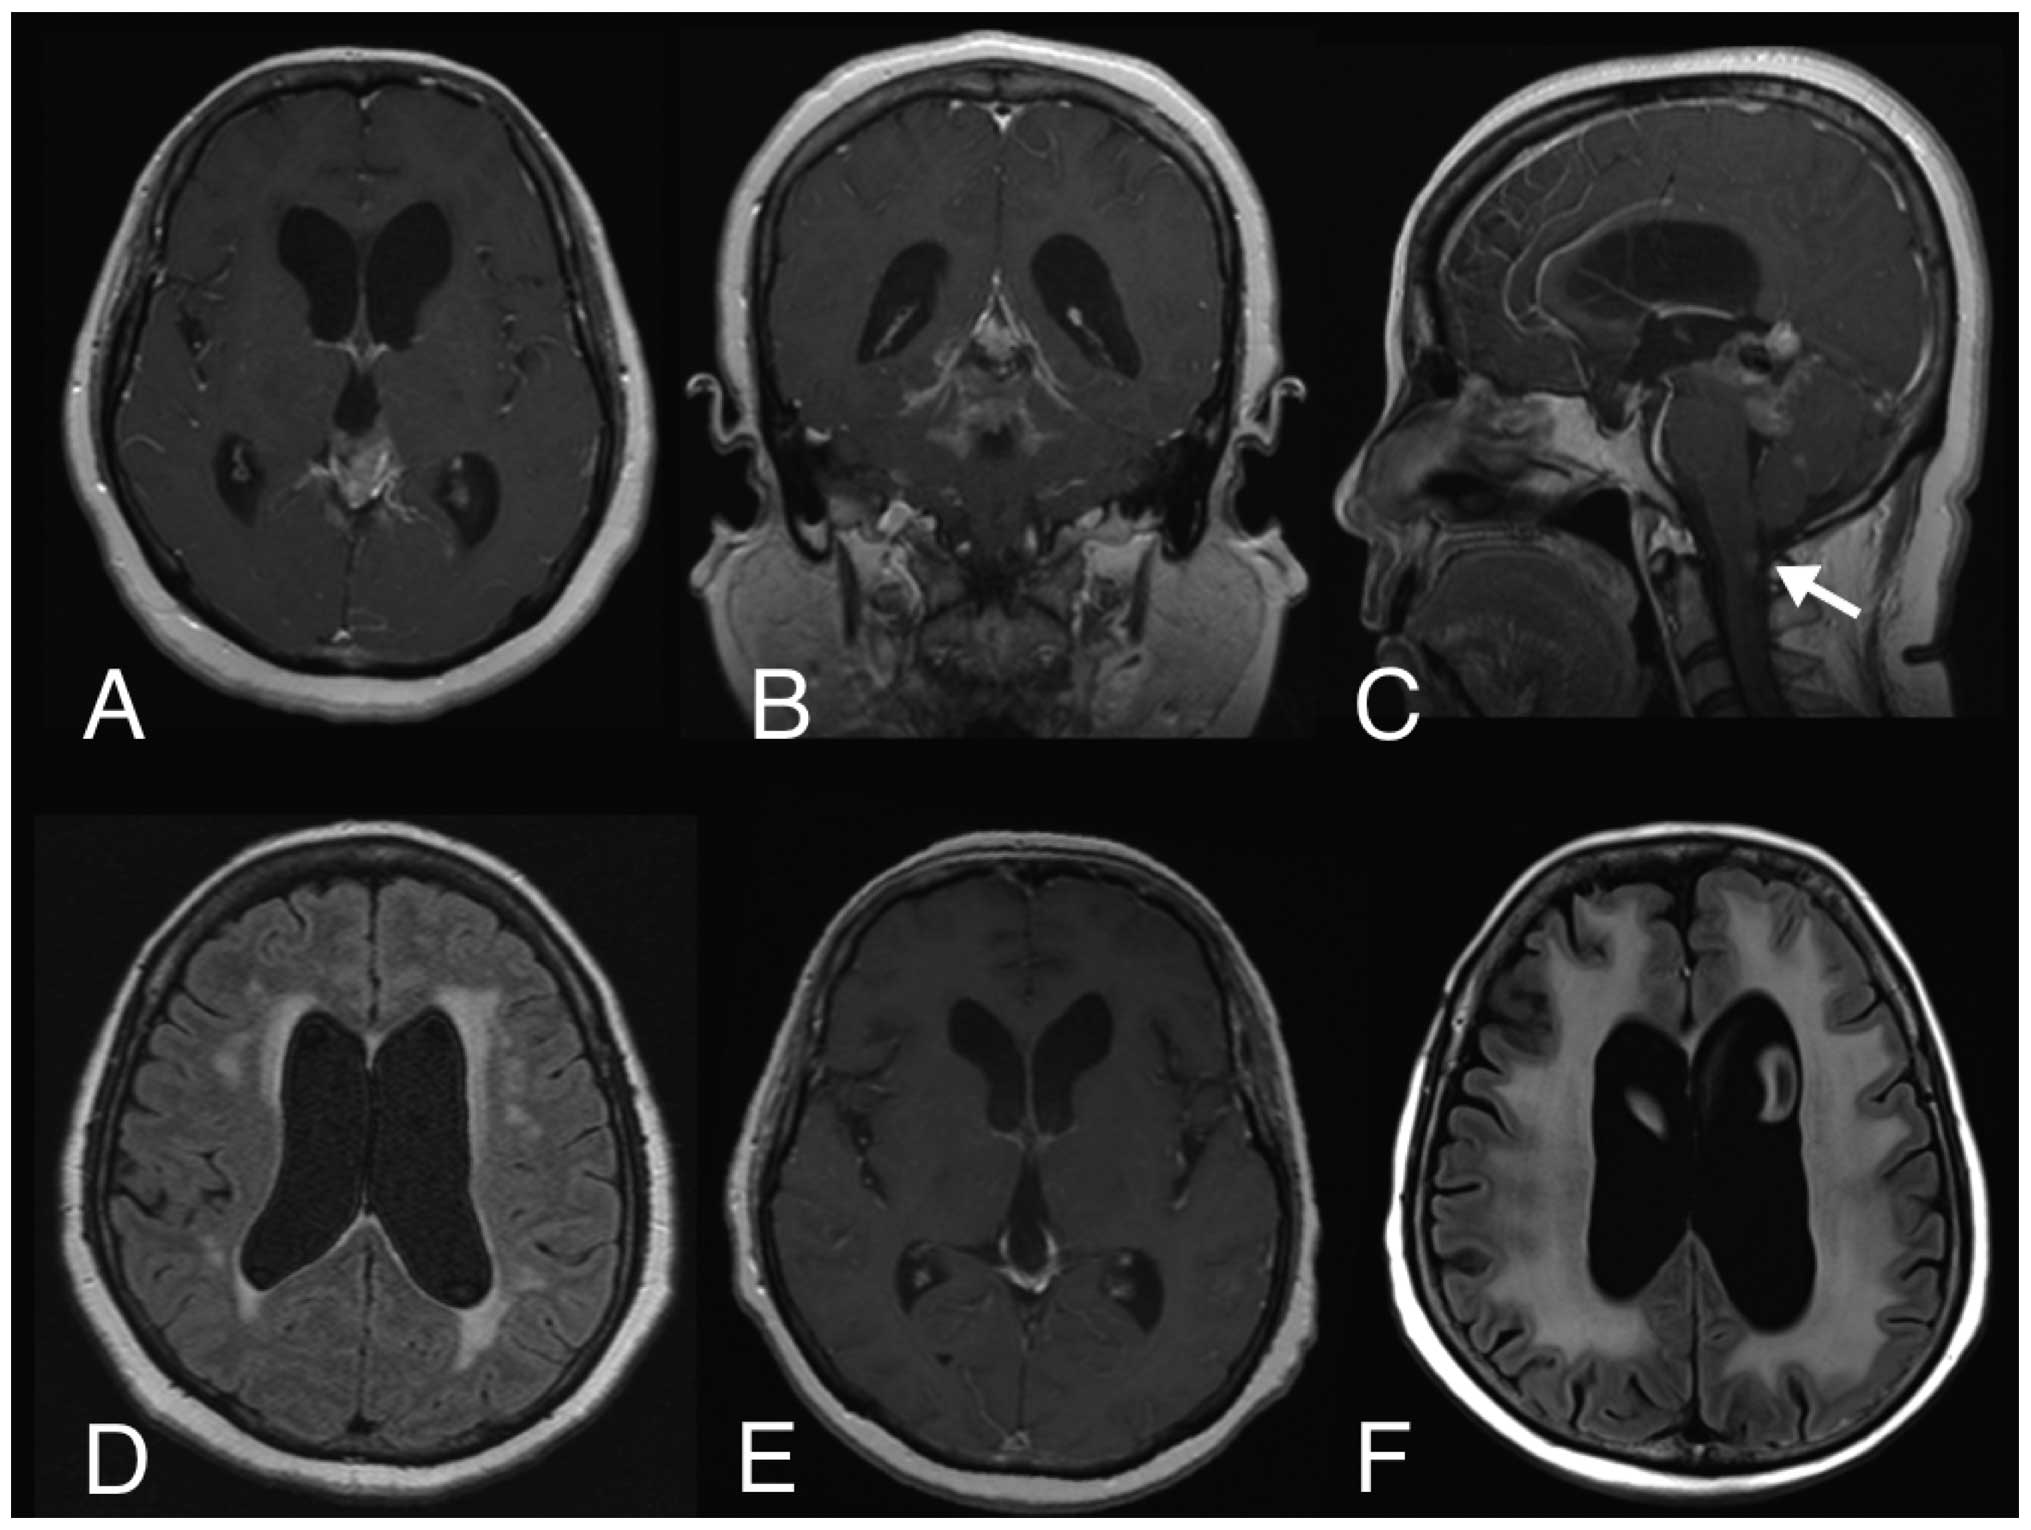

Table II outlines the late adverse effects after treatment. The two patients who received 36 Gy of craniospinal irradiation and 18 Gy of whole-ventricular irradiation had evidence of cerebral white matter abnormalities in MRI and grade 3 cognitive disturbance according to RTOG and CTCAE toxicity grading, at 5–7 months and at 4–6 years after radiation therapy (Table II, Fig. 1). Although the patient who received only 34.2 Gy of whole-ventricular irradiation had evidence of cerebral white matter abnormalities at 6 months after radiation therapy, the patient exhibited no evidence of a neurocognitive disorder, even 9 years after the treatment. The patients who were irradiated locally had no evidence of cerebral white matter abnormalities or neurocognitive disorders. The two patients who received craniospinal and whole-ventricular irradiation also exhibited evidence of hypopituitarism after treatment: one developed a growth hormone deficiency 8 months after radiation therapy and the other developed a thyroid-stimulating hormone deficiency 7 years after radiation therapy. However, the latter patient already had a lack of growth hormone when he was diagnosed with PPTID. There were no reported cerebrovascular disorders after treatment.

Figure 1

Example of treatment response and a late adverse effect. (A–D) Magnetic resonance imaging at the time of diagnosis (Tables I and II, case 3). (A, B and C) Contrast-enhanced T1-weighted imaging prior to treatment revealed spinal dissemination on the dorsal side of the medulla oblongata, appearing as a contrast-enhanced region (arrow). (D) The patient had slight periventricular white matter abnormalities on fluid-attenuated inversion recovery (FLAIR) magnetic resonance imaging. (E) Contrast-enhanced T1-weighted magnetic resonance imaging 2 months after treatment demonstrated a complete response. (F) The patient clearly showed exacerbated periventricular white matter abnormalities on FLAIR imaging and gradually developed a neurocognitive disorder in the 6 years following treatment.